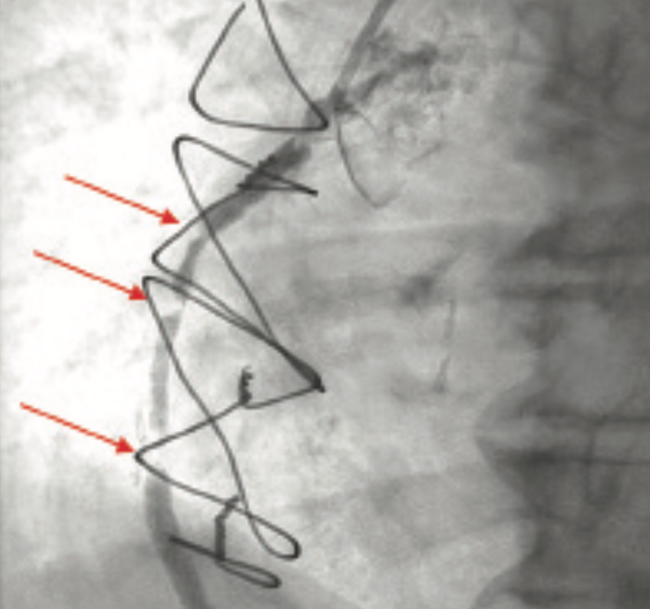

Coronary artery perforation (CAP) is a rare but serious, and potentially fatal, complication of percutaneous coronary intervention (PCI). CAP occurs when an intimal tear or dissection penetrates the arterial wall. Previous studies estimate the incidence of CAP during PCI is between 0.2 and 0.6%.1-4 While this is a rare event, it can lead to life-threatening complications, including cardiac tamponade.

CAPs are typically classified according to the Ellis Classification System:

Type I: Extraluminal crater without extravasation